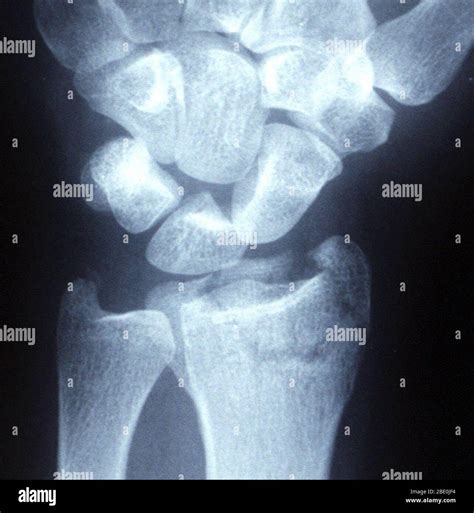

The human wrist is a complex arrangement of eight small carpal bones and the ends of the two forearm bones, the radius and the ulna. When you suffer a fracture broken wrist, your body immediately signals that something is wrong through a series of distinct symptoms. Distinguishing between a severe sprain and a fracture can be difficult without imaging, which is why professional medical attention is non-negotiable.

When you visit an urgent care clinic or emergency room, the physician will perform a physical examination to check for nerve integrity and blood flow. However, because a fracture broken wrist cannot be diagnosed by touch alone, imaging is the gold standard for treatment planning.

X-ray Provides a clear image of bone alignment and fracture lines.